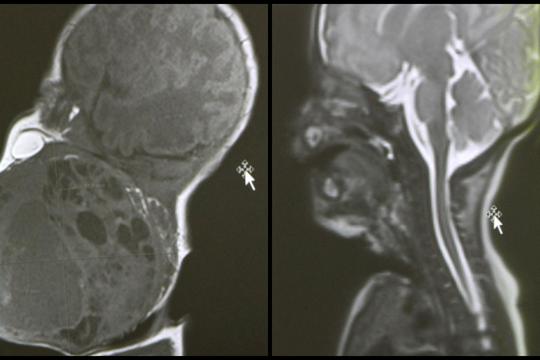

Prema nalazima magnetske rezonance prije poroda, tumor je bio gotovo veličine djetetove glave i zatvarao je dišne puteve. Dijete bi bilo životno ugroženo ako bi se rodilo normalnim putem, stoga je tim liječnika morao razraditi i biti spreman na nekoliko varijanti liječenja, a na kraju je profunkcionirala prva opcija.

"Tijekom carskog reza, kada je otvorena maternica, djetetova glava je izvađena, a ostatak tijela je bio u maternici pa je dijete bilo vezano za placentu i putem pupkovine dobivalo kisik. Pristupili smo glavi i pokušavali uspostaviti dišni put", objasnila je pročelnica Zavoda za neonatologiju i intenzivnu medicinu Ruža Grizelj. U sali je, kaže, bilo 20 ljudi.

"Kada smo bili sigurni da smo uspostavili umjetno disanje preko tubusa koji je stavljen u dušnik, tada smo rekli - idemo poroditi dijete. Dijete je izvađeno kompletno izvan maternice, podvezana je pupkovina i nakon što smo ga stabilizirali, istoga dana je učinjeno kompletno odstranjenje tumora s obzirom na to da smo nekoliko sati nakon samog poroda primijetili u intenzivnoj da se tumor povećava", rekla je Grizelj.

Voditelj Odjela za fonijatriju Ratko Prstačić pojasnio je da je patohistološka dijagnoza pokazala da se radi o teratomu, generalno dobroćudnom tumoru, ali s potencijalnom malignom opasnošću pa će dijete trebati onkološko praćenje, no druga terapija trenutačno nije potrebna.